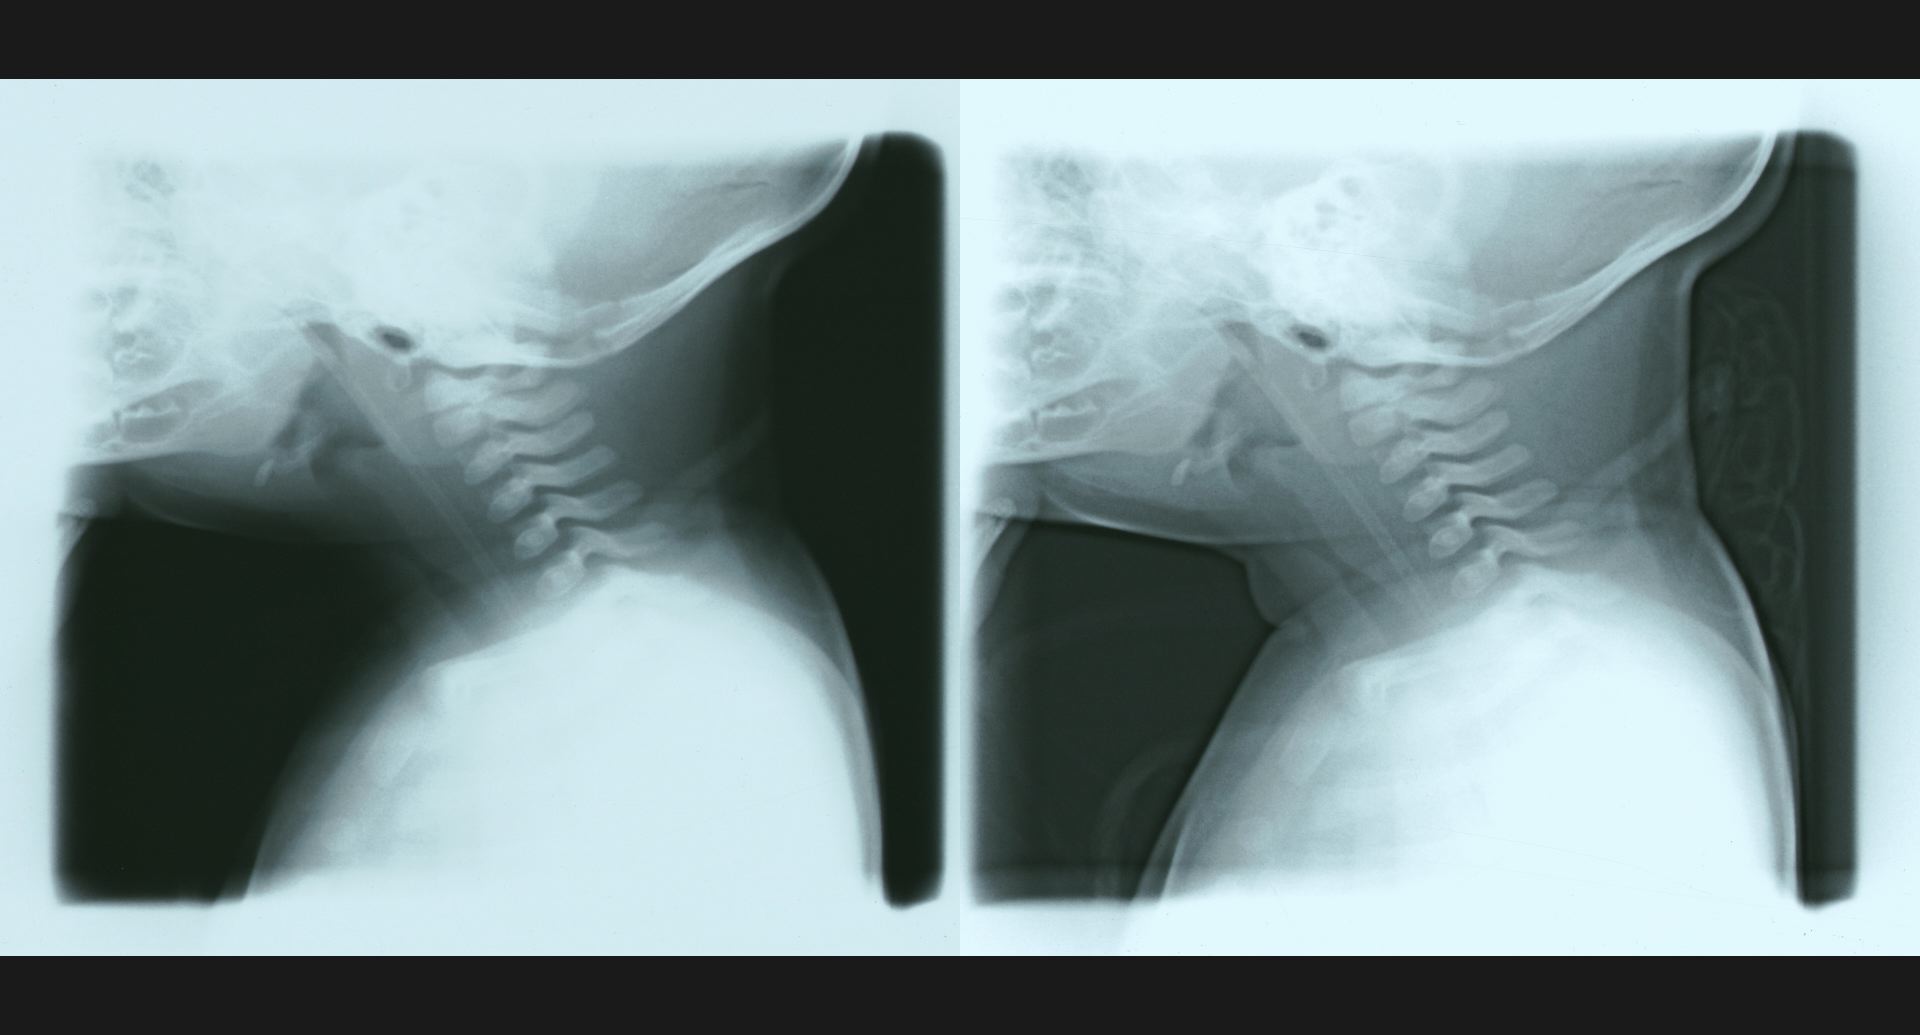

:Phantom discdisc内の透亮像。spur。

fig.15(55KB)

:Fibrous dysplasia骨頭のtrabeculation。病変部。